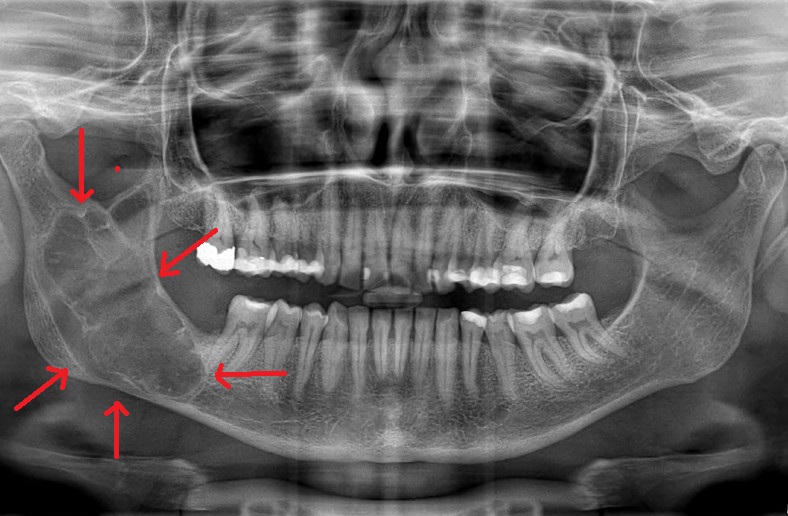

Η διάγνωση συνήθως περιλαμβάνει κλινική εξέταση, ακτινογραφίες, και σε ορισμένες περιπτώσεις βιοψία για την επιβεβαίωση της φύσης του όγκου.